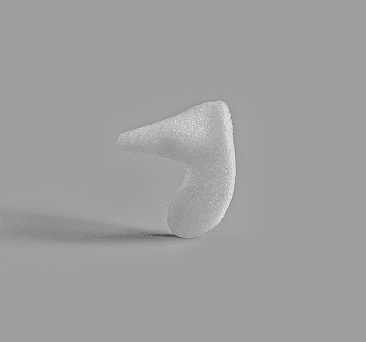

Enophtalmos Wedge